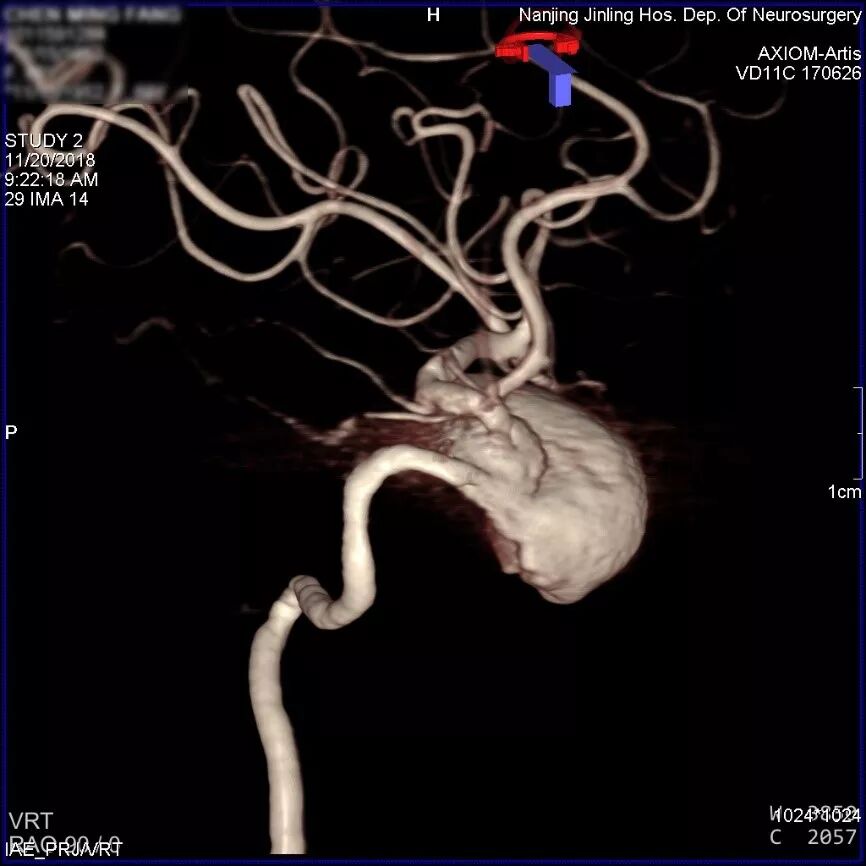

患者取平卧位,气管插管全麻,右侧股动脉穿刺,置入6F 70cm长鞘至左侧颈总动脉,5F Navien中间导管在Marksman引导下超选至动脉瘤近端,行3D旋转造影显示:左侧颈内动脉海绵窦段大型血栓性动脉瘤。

为什么要用到微导管张鑫教授:“球囊锚定微导管辅助到位”技术在Pipeline Flex治疗复杂动脉瘤手术中的应用_https://www.jmylbn.com_新闻资讯_第4张

3D旋转造影

显影部分动脉瘤大小约31.6*23.1mm,瘤颈宽6.4mm,载瘤动脉远端直径约为2.93mm,近端约为2.89mm。根据造影情况决定行血流导向装置置入术,选择Pipeline Flex 3.0mm*35mm。